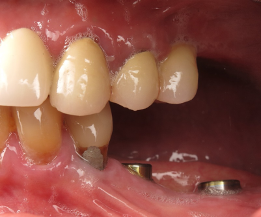

(14.) Three-month postoperative occlusal and buccal views of the healed implants at site Nos. 19 and 21.

Figure 14

(15.) Three-month postoperative occlusal and buccal views of the healed implants at site Nos. 19 and 21.

Figure 15

A healthy 60-year-old female presented for an emergency evaluation because she was experiencing pain associated with tooth No. 20. It was mobile, malposed, and given a diagnosis of irreversible pulpitis. In addition, teeth Nos. 19 and 21 had been missing for more than 5 years. After the evaluation, a discussion revealed that the patient desired implant reconstruction of the lower left quadrant. During this initial visit, a CBCT scan was obtained, and the virtual restoration-driven implant planning was completed, confirming that extraction of tooth No. 20 with robot-assisted immediate implant placement at the sites of teeth Nos. 19 and 21 was a viable option (Figure 9 through Figure 13). Splint placement, CBCT capture of the fiducial array, calibration, and landmark confirmation were completed as described in the first case report. Following the administration of intravenous sedation and local anesthesia, tooth No. 20 was atraumatically extracted. Flap access was obtained from the site of tooth No. 18 to the site of tooth No. 22, and robot-assisted surgical implant placement was completed at the sites of teeth Nos. 19 and 21. Intraoperatively, guide pins were placed to evaluate the position of the proposed osteotomies, and it was determined that both implants should be tilted buccally by 0.4 mm. The necessary changes were made in the software application, and the new implant placement plan was immediately ready for robotic implementation. The implants were robotically delivered to their planned positions at the sites of teeth Nos. 19 and 21 and torqued to initial stability at 50 Ncm and 45 Ncm, respectively (Figure 14 and Figure 15). Healing abutments were placed, and the tissue was closed primarily. In this case, robotic assistance facilitated the performance of surgery on the same day that the patient initially presented and permitted intraoperative modifications to be made.